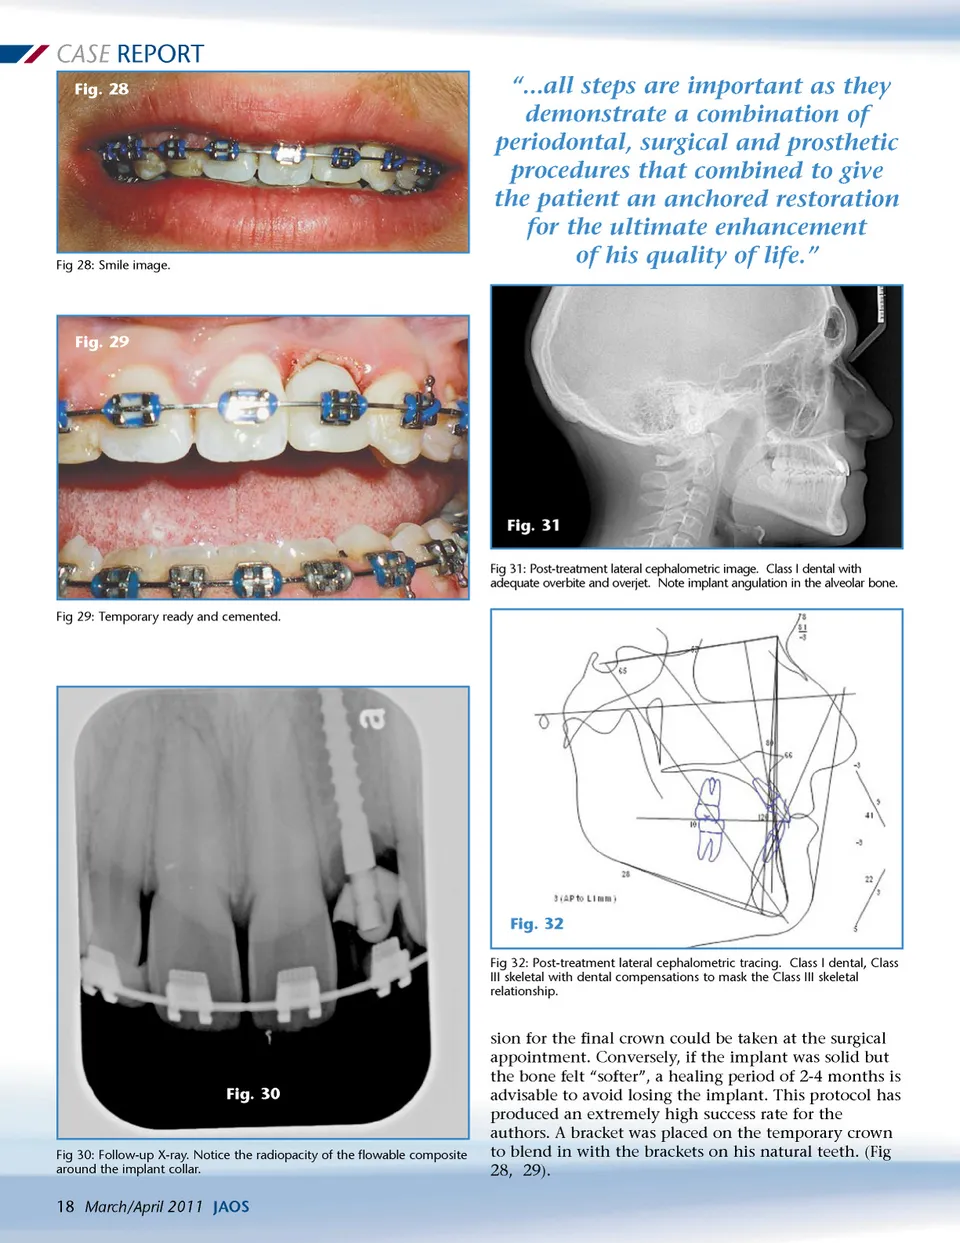

CASE REPORT Fig. 28 Fig 28: Smile image. “...all steps are important as they demonstrate a combination of periodontal, surgical and prosthetic procedures that combined to give the patient an anchored restoration for the ultimate enhancement of his quality of life.” Fig. 29 Fig. 31 Fig 31: Post-treatment lateral cephalometric image. Class I dental with adequate overbite and overjet. Note implant angulation in the alveolar bone. Fig 29: Temporary ready and cemented. Fig. 32 Fig 32: Post-treatment lateral cephalometric tracing. Class I dental, Class III skeletal with dental compensations to mask the Class III skeletal relationship. Fig. 30 Fig 30: Follow-up X-ray. Notice the radiopacity of the flowable composite around the implant collar. sion for the final crown could be taken at the surgical appointment. Conversely, if the implant was solid but the bone felt “softer”, a healing period of 2-4 months is advisable to avoid losing the implant. This protocol has produced an extremely high success rate for the authors. A bracket was placed on the temporary crown to blend in with the brackets on his natural teeth. (Fig 28, 29). 18 March/April 2011 JAOS